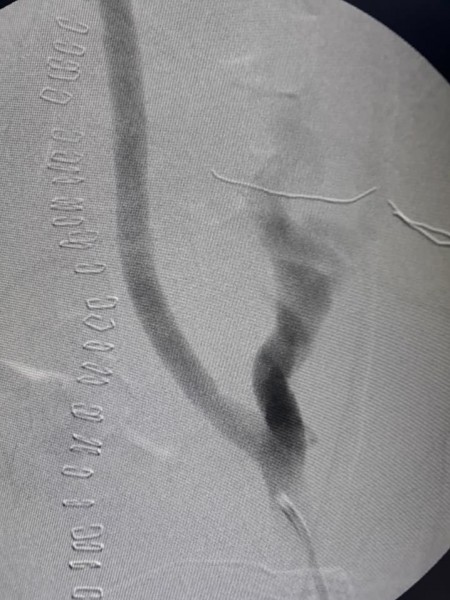

انفرد فريق طبي مشترك من قسم جراحة الأوعية الدموية بكلية الطب بجامعة أسيوط ومعهد جنوب مصر للأورام بالجامعة بإجراء أول عملية جراحية فى مصر لشاب فى الثلاثين من عمره لإزالة ورم يمتد من أعماق الحوض والأعصاب إلى البطن حتى مستوى الكليتين خلف الغشاء البريتونى ، ومسبباً انسداد بأوردة الحوض الحرقفية وانسداد تام بالوريد الأجوف السفلى حتى أوردة الكلية ومتشعباً بين شرايين الحوض والبطن مسبباً انسداد بشرايين الطرف السفلى الأيمن وملتصق بالعمود الفقري وعضلاته ، و الذي تم محاولة استئصاله من قبل حيث كان عمر المريض عامين و لكن دون جدوى ، جاء ذلك تحت رعاية الدكتور طارق الجمال رئيس الجامعة و الدكتور سامي عبد الرحمن عميد معهد جنوب مصر للأورام.

و من جانبه أكد الدكتور عثمان محمود أحمد مدرس جراحة الأوعية الدموية ومسئول الفريق الطبي لجراحة الأوعية الدموية بالعملية أن العملية استغرقت 10 ساعات تم خلالها استئصال الورم كاملا ثم تم زرع شريان لأعاده الاتصال الدموي للطرف السفلى الأيمن ثم تبعها عمل تصميم من شرايين صناعية تم توصيلها في تصميم فريد وباستخدام وصلات مدعومة خارجياً حتى تسمح بسريان الدم وعدم تجلطه وتتماشى مع ضعف عضلة القلب وتم زرع هذا التصميم لإعادة الاتصال الدموي لكل أورده الحوض والوريد الأجوف السفلى حتى أوردة الكليتين ، ثم خرج المريض إلى العناية المركزة بمعهد جنوب مصر واستعاد نشاطه اليومي بعد 48 ساعة بصحة جيده .